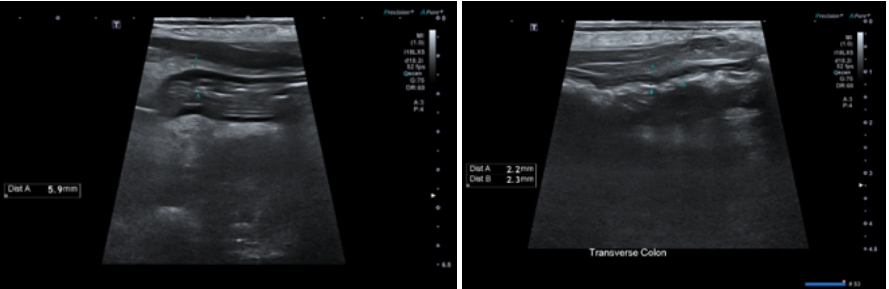

복부 초음파 결과

- 췌장 ; 전반적으로 비대되고, 저에코성 변화 확인됨. 또한 췌장 주변 상복부 위주로 뚜렷한 복막염 확인되었습니다.

- 위장관계 ; 췌장과 인접한 유문부, 십이지장의 경미한 근육층 비후, 주변부 심한 복막염 확인되었습니다.

> 공장은 일부 분절에서 경미한 근육층 비후 확인되었습니다. 가로 결장의 경미한 벽 비후 확인되었으며 오름, 내림 결장은 양호한 상태였습니다.